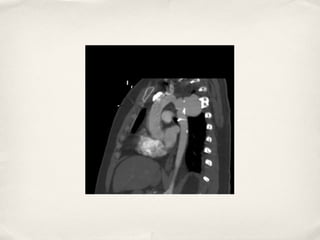

Aortic Arch Tear

Aortic Arch Transection

✤ Common in deceleration ( blunt ) type injuries

✤ Most common site is the ligamentum attachment ( isthmus)

✤ Free rupture is incompatible with life

✤ Contained rupture is associated with increased risk of free rupture

✤ Usually associated with other life threatening injuries

Aortic Arch Transection ✤ Common in deceleration ( blunt ) type injuries ✤ Most common site is the ligamentum attachment ( isthmus) ✤ Free rupture is incompatible with life ✤ Contained rupture is associated with increased risk of free rupture ✤ Usually associated with other life threatening injuries